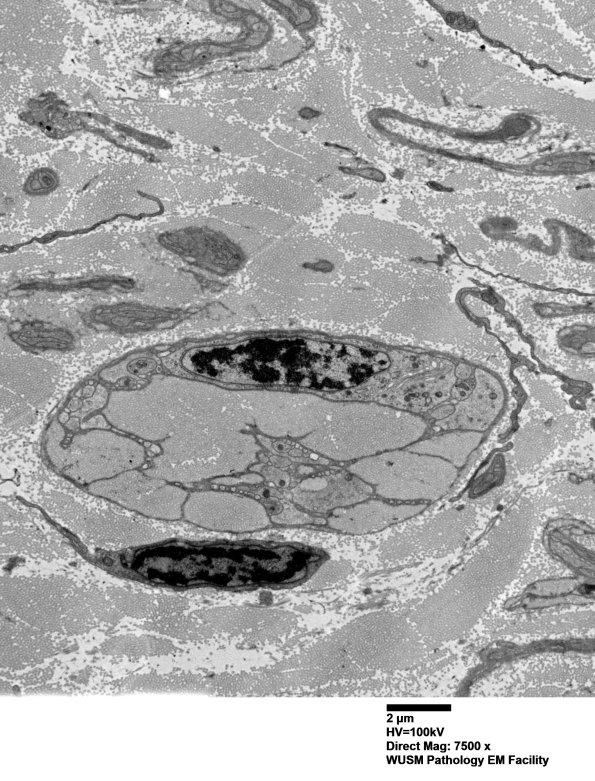

Washington University Experience | PERIPHERAL NEUROPATHY | 4 AXONAL DEGENERATION | 3 Electron Microscopy | 7A3B Chronic Degeneration (Case 33) ural_041 - Copy

This appears to be a Schwann cell with large collections of collagen delimited by its extensive processes. (electron micrographs)